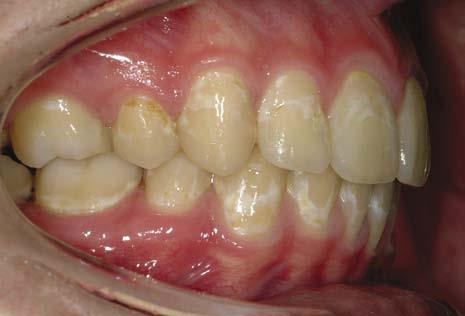

Juvenile rheumatoid arthritis

An inflammatory arthritis occurring before the age of 16 years and involving the temporomandibular joints can result in the development of a severe class II malocclusion due to restricted growth of the mandible (Fig. 1.12).